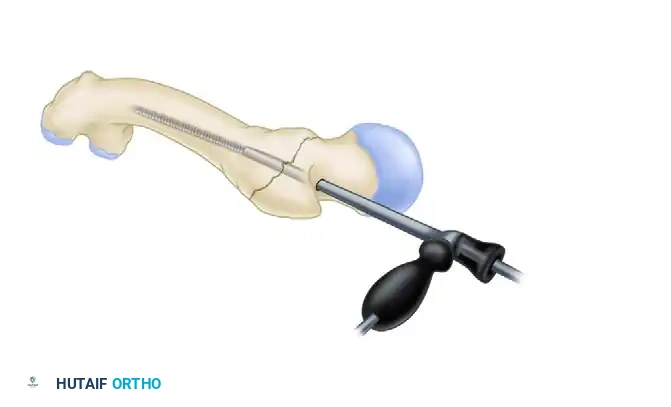

Placement of the nail beginning with the insertion guide facing anteriorly to accommodate the femoral bow.

- Crucial Maneuver: As with all antegrade femoral nails inserted through a trochanteric portal, begin insertion with the guide facing anteriorly. This utilizes the anterior bow of the nail to navigate the proximal geometry more easily.

- Once the nail has been inserted approximately halfway down the intramedullary canal, rotate the guide 90 degrees laterally.

- Monitor the insertion of the nail meticulously with lateral fluoroscopy to avoid anterior cortical perforation, a known complication in patients with an excessive anterior femoral bow.